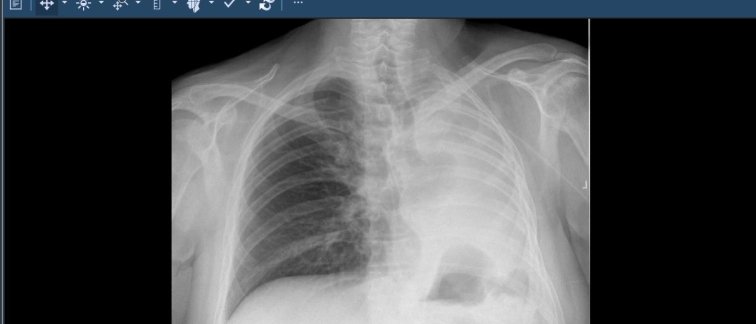

Patiënten worden voor een specifieke behandeling regelmatig verwezen naar een ander ziekenhuis. De digitale medische beelden en beeldverslagen van de patiënt die voor de behandeling nodig zijn, worden dan via een dvd verzonden naar dit ziekenhuis.

Visser vult aan: “Dat je niet meer hoeft te wachten op de beelden uit andere ziekenhuizen maar ze gelijk via je eigen systeem kunt bekijken, is een enorme verbetering. Het voorkomt ook dat patiënten meerdere keren hetzelfde onderzoek moeten ondergaan. De resultaten van de pilot waren positief. Volgend jaar willen we dit bij andere specialismen gaan gebruiken.” Uiteraard wordt medische informatie alleen uitgewisseld wanneer de patiënt hiervoor toestemming heeft gegeven en er sprake is van een behandelrelatie.